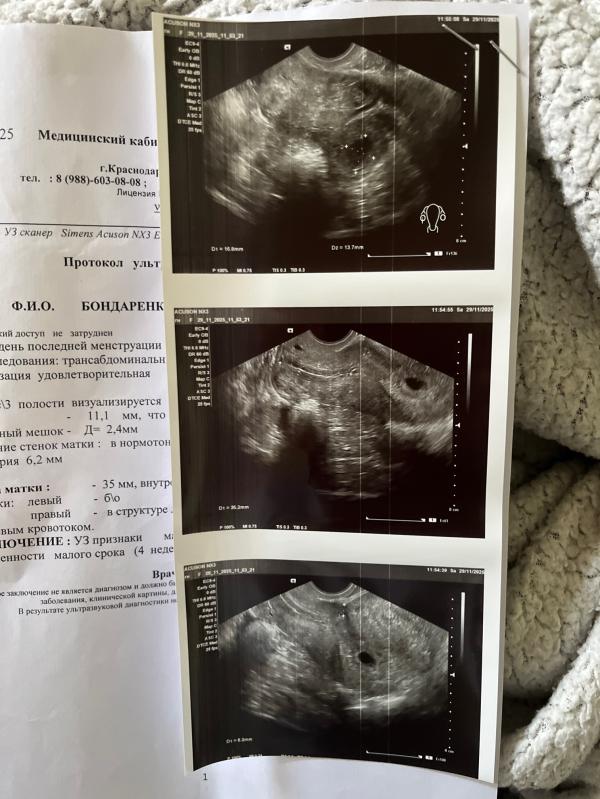

По узи хорошо все , была угроза так как ниже плодное яйцо стало